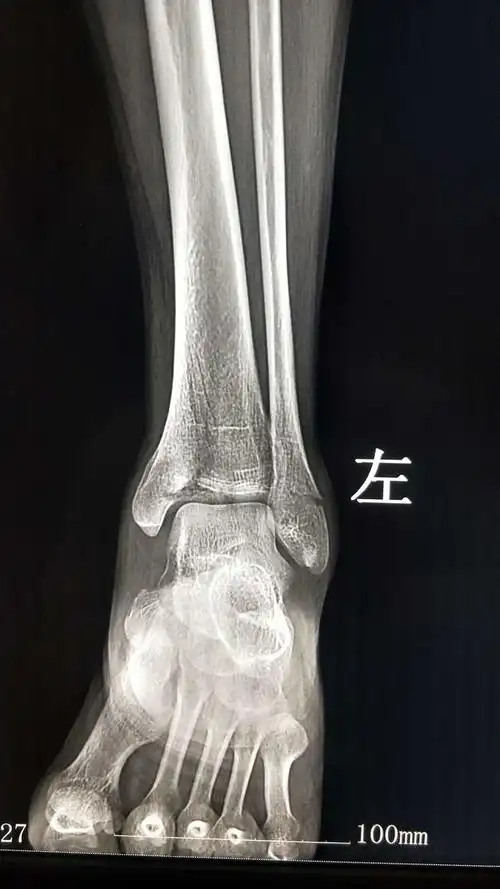

术后x线片术后切口现患者已出院,切口愈合可,左小腿可借助拐杖下地